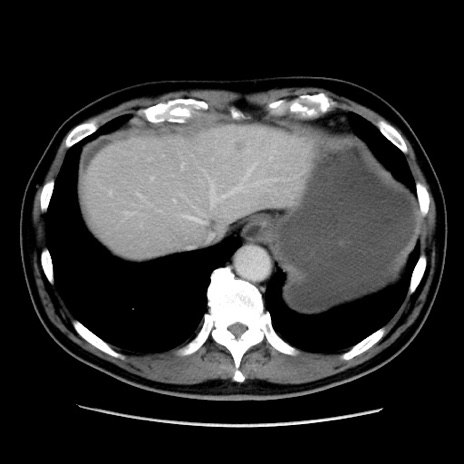

症例16(横断像)

【症例】 70歳代男性

【主訴】 腹痛、嘔吐

【現病歴】 約1ヶ月前より間欠的に腹痛と嘔吐あり、当院消化器内科を受診したところCTで多発する肝臓のLDAを指摘され、精査中であった。以降は消化器症状は安定していたが、2日前より嘔気と腹痛があり、同日より排便・排ガスが消失した。改善認めず、 本日、救急外来を受診した。

【既往歴】 大腸ポリープ切除後。

【身体所見】意識清明・会話良好、BT 36.3℃、BP 127/80mmHg、 P 80bpm、腹部:膨満あり、平坦・軟、上腹部正中および下腹部正中に圧痛あり、反跳痛なし、筋性防御なし。

【データ】WBC 7200、CRP 0.77